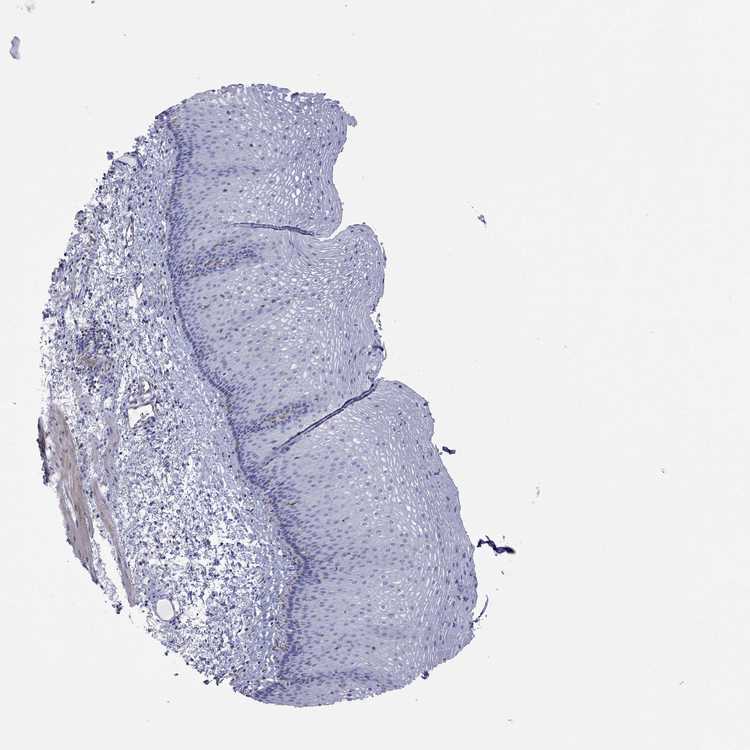

ESOPHAGUS - Antibody stainingi

Antibody staining in the annotated cell types in the current human tissue is reported as not detected, low, medium, or high, based on conventional immunohistochemistry profiling in selected tissues. This score is based on the combination of the staining intensity and fraction of stained cells.

Each image is clickable and will lead to virtual microscopy that enables deeper exploration of all samples and also displays staining intensity scores, fraction scores and subcellular localization as well as patient and tissue information for each sample.

Antibody HPA017345Antibody HPA064805

Squamous epithelial cells Not detectedNot detected